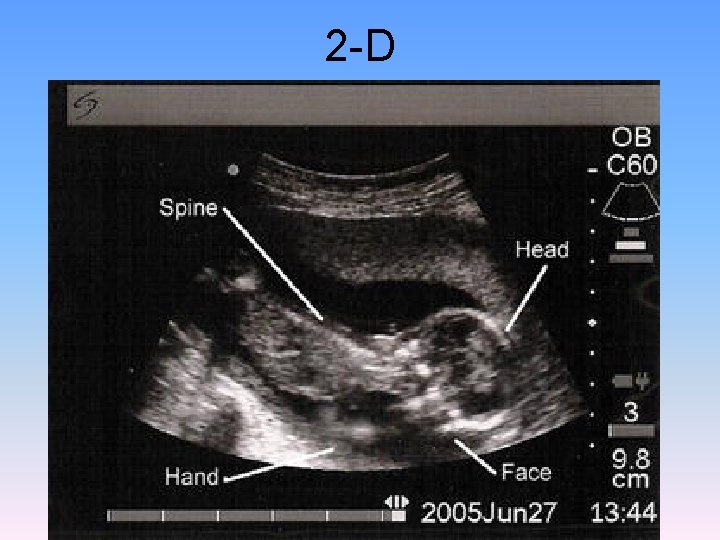

2 -D

3 -D and 4 -D National Geographic Channel In The Womb